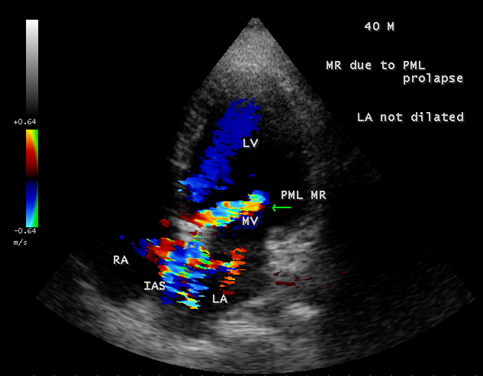

Case 1. PML (posterior mitral leaflet) prolapse causing mitral regurgitation without LA (left atrium) enlargement as shown in Figures 1 and 2 (non-rheumatic) in a 40-year old male. The patient was advised lifelong penicillin prophylaxis and periodic follow up.

Figure 2. Apical four chamber view showing the mitral regurgitation swirling around IAS (interatrial septum) in a 40-year old male due to PML (posterior mitral leaflet) prolapse. LA (left atrium not dilated)